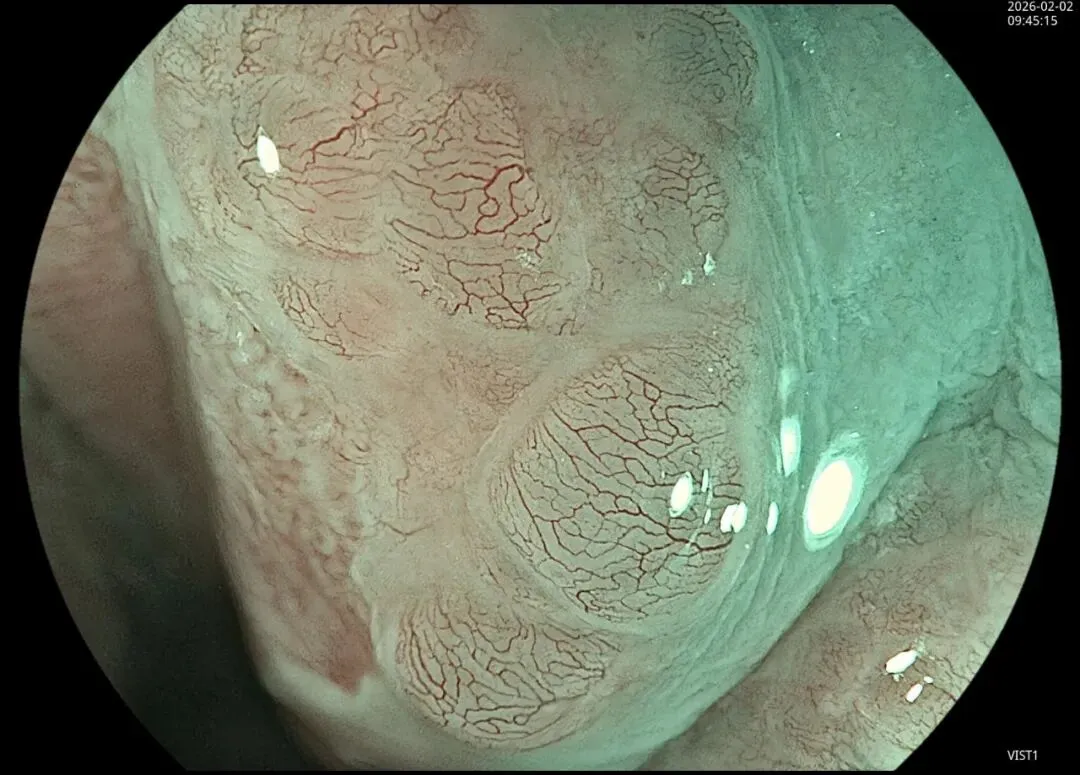

这一期不用码字,挺好的,很可惜一直没机会听过胡导讲的关于这个“花环征”的大课,学习内容来源于雨夜大师的号花环征:AIG背景的胃食管结合部的黄色颗粒状隆起及半透明“泡状”改变

补充自己在两例A型胃炎/AIG 观察到的“花环征”,巩固下学习效果。。。

2.窄带光下可见颗粒状隆起呈褐色改变,放大可见细微网状血管结构及半透明“泡状”改变